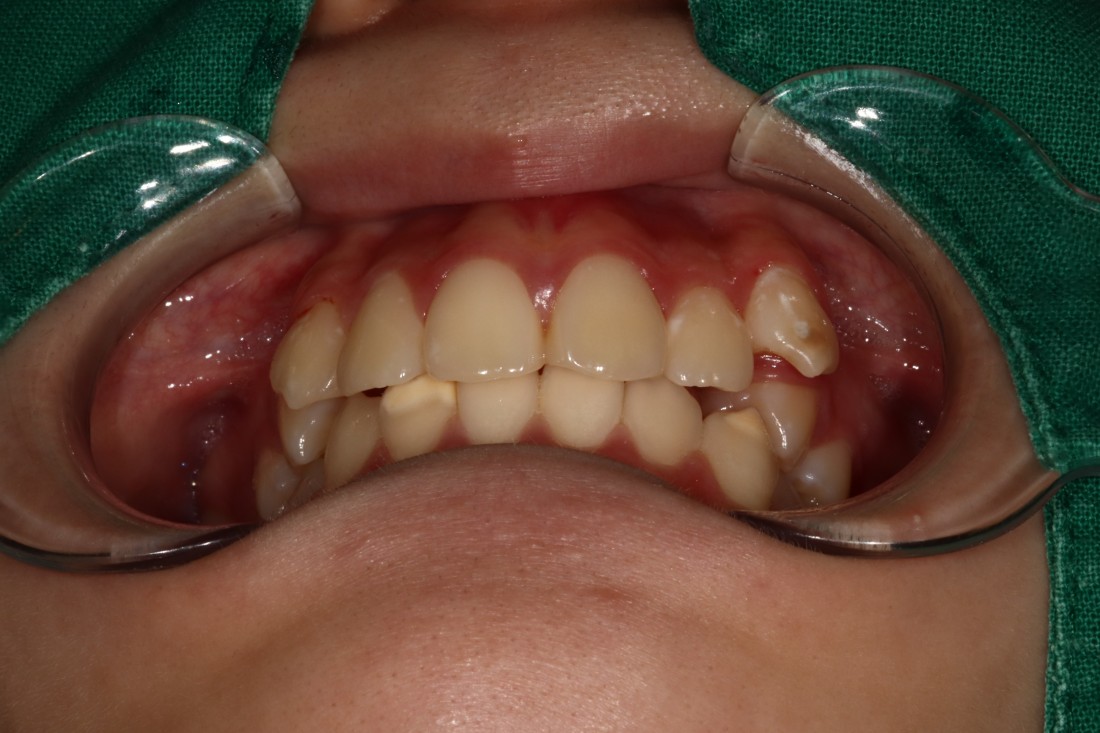

덧니는 과거에는 귀여운 이미지를 줘서

선호하기도 하였지만,

요즘은 고른 치열을 만들어서

세련된 외모를 완성하는 것이

필수 트렌드가 되고 있습니다.

광주 교정치과에서는

3차원 105항목 정밀검사를 통해

발치교정 / 비발치교정 을 포함하여

정확한 치료계획을 세우고 있습니다.